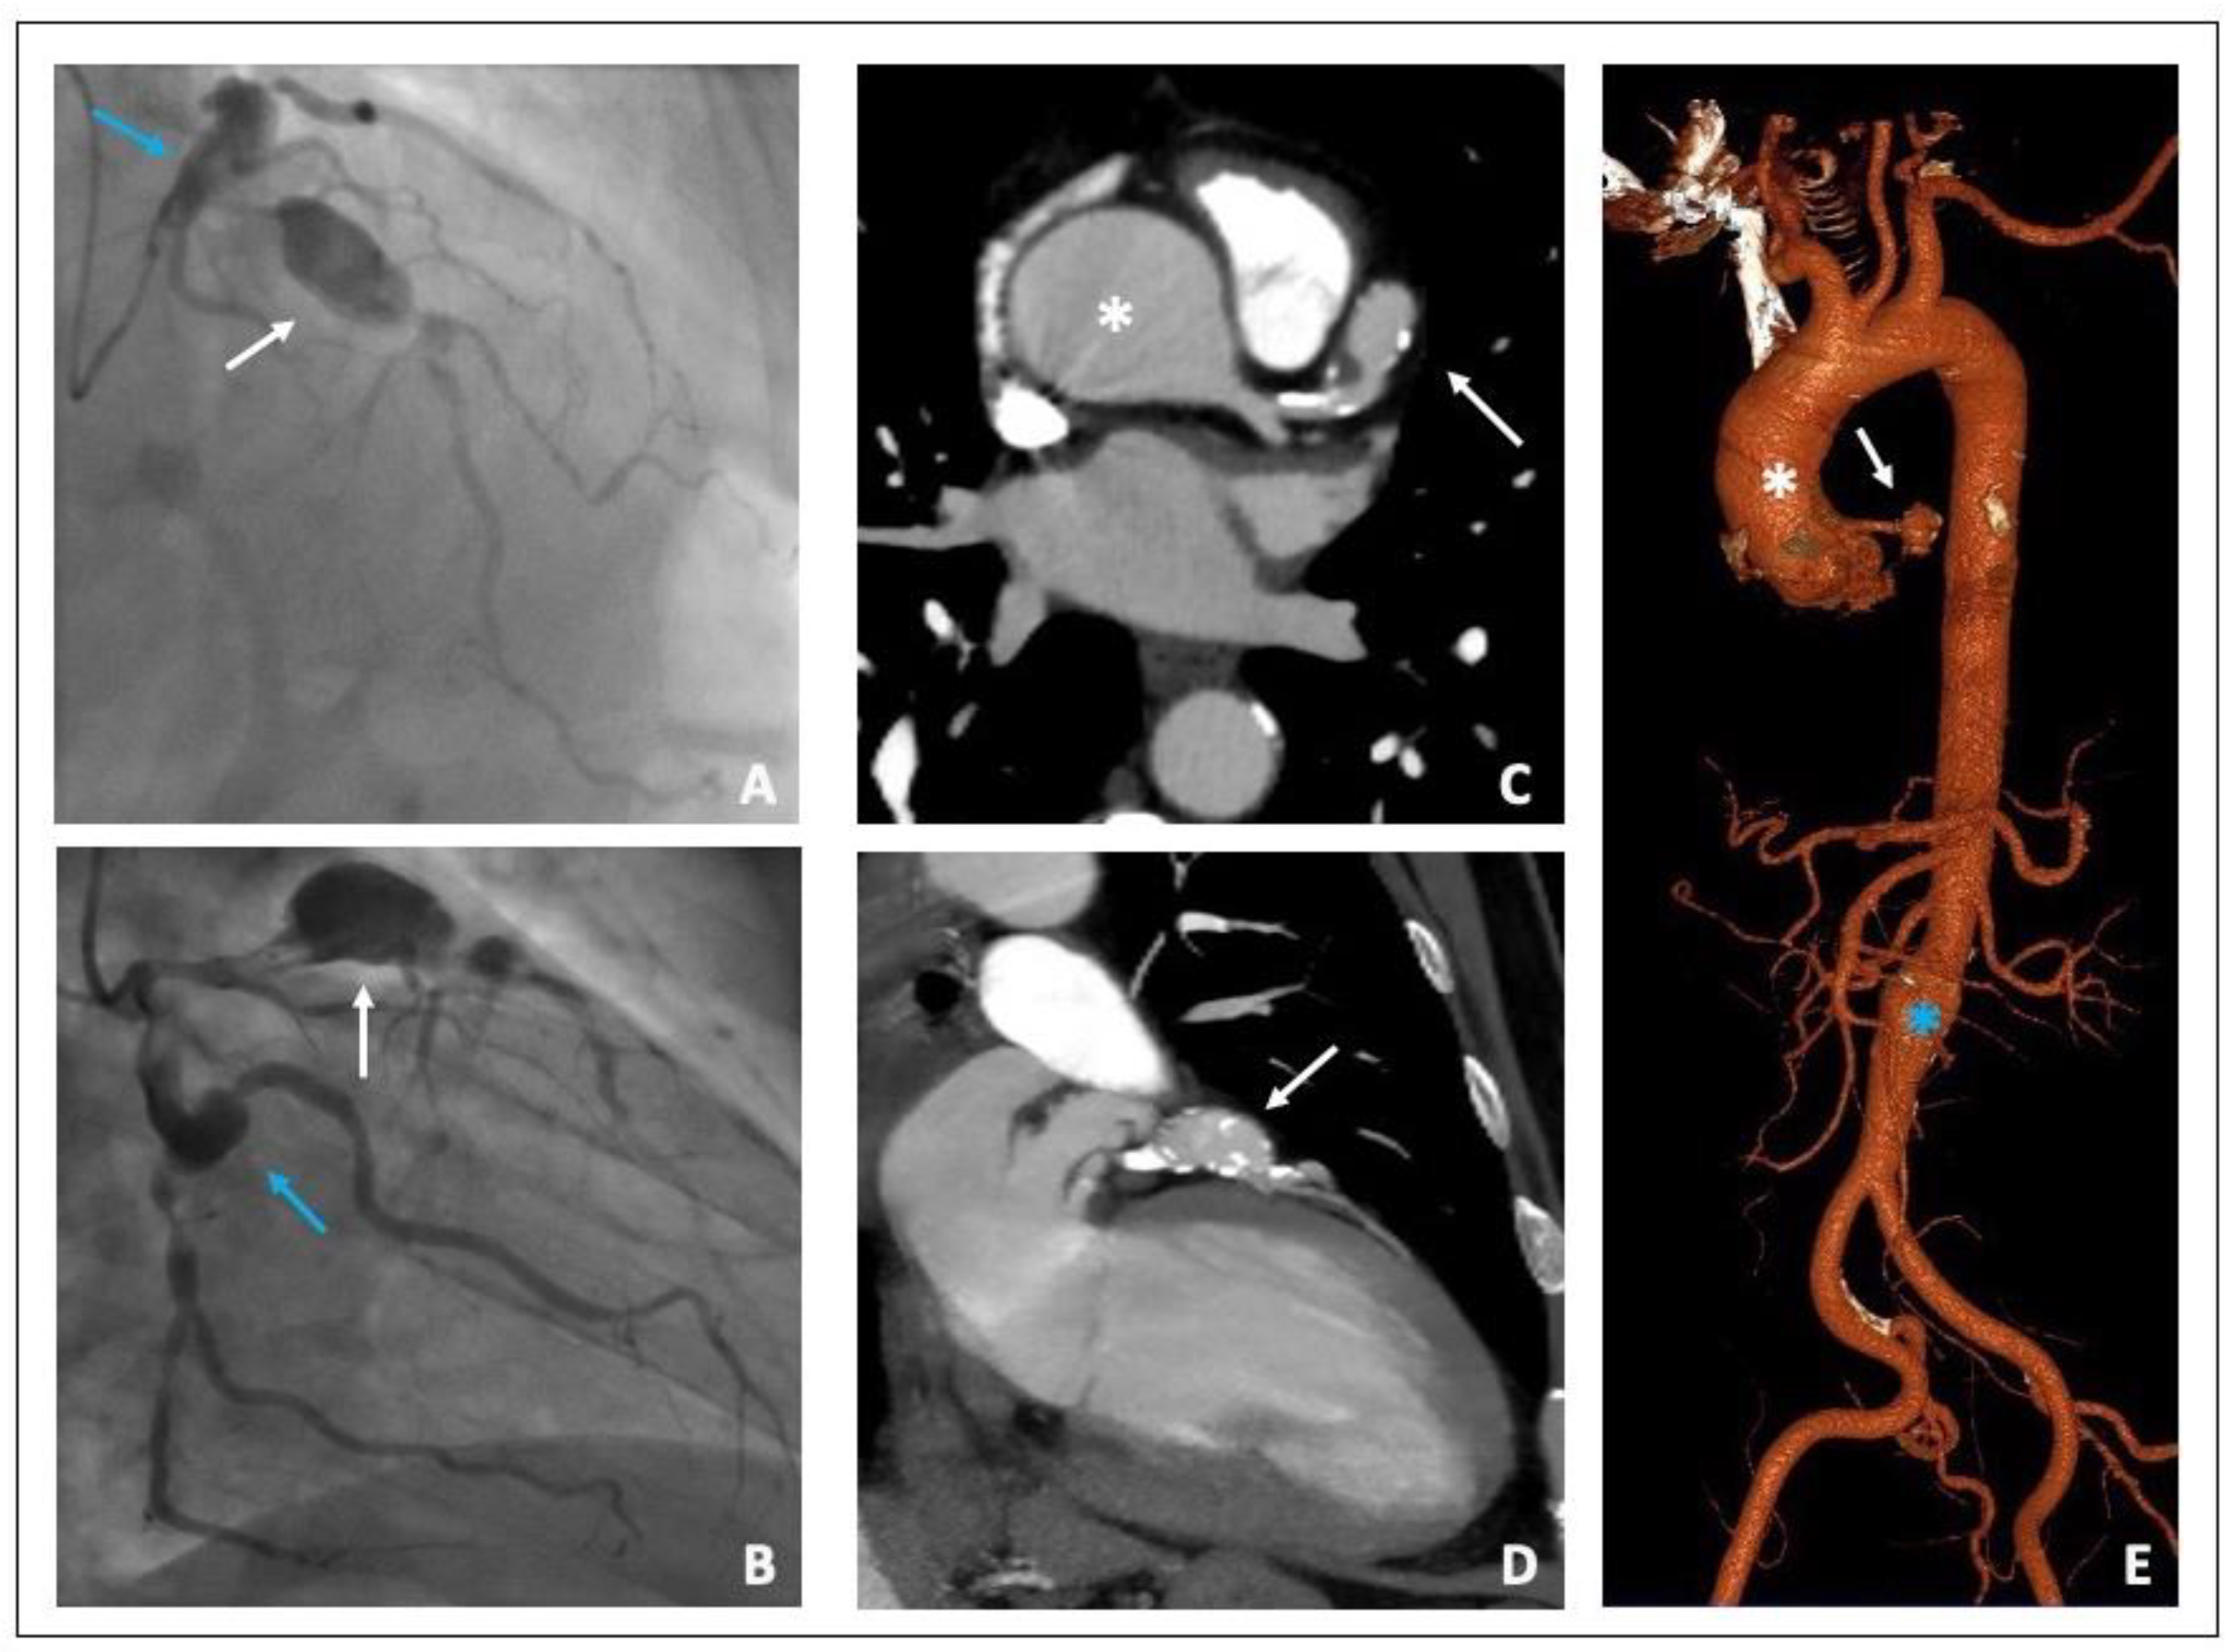

6. Case 1